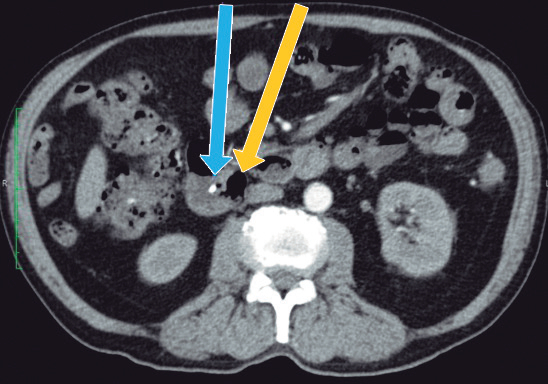

Con los hallazgos mencionados, se realizó el diagnóstico de colangitis grado II (sobre la base de los criterios diagnósticos y de severidad de las guías de Tokyo),6 y se inició tratamiento antibiótico. Posterior a las primeras 24 horas del diagnóstico, el paciente fue sometido a CPRE, en la que se identificaron tres divertículos duodenales periampulares. Debido a que la canulación fue difícil, tuvo que realizarse, durante el procedimiento, la técnica de rendez-vous (guiada por ecografía y fluoroscopía), utilizando el acceso transparietohepático para lograr el ingreso a la vía biliar. En la colangiografía, el conducto biliar se encontraba dilatado (10 mm) y no se evidenciaron imágenes por defecto de relleno. Se realizó una esfinterotomía mínima y se colocó una prótesis biliar plástica de 10 Fr x 7 cm para poder asegurar un adecuado drenaje de la vía biliar. El paciente evolucionó favorablemente. Al momento del alta no presentaba dolor abdominal, había normalizado los valores de leucocitos y PCR, y los valores de colestasis se encontraban en descenso. En los controles posteriores, el paciente presentó dolor abdominal esporádico en el CSD, pero el examen físico y los análisis de sangre no mostraron mayores alteraciones. El paciente contaba, además, con una tomografía abdominal con contraste, que no aportó información adicional a la evidenciada en la CPRM (Figuras 2 y 3).

Por la edad del paciente, el hallazgo de los DDP y la dilatación del conducto pancreático principal, se decidió complementar el estudio diagnóstico con la realización de una ultrasonografía endoscópica (USE) biliopancreática, para descartar la presencia de neoplasias pancreatobiliares no evidenciadas en los estudios previos de imágenes. La USE biliopancreática mostró la presencia de un DDP de gran tamaño, dilatación coledociana y escaso barro en la vesícula biliar. El páncreas no presentaba alteraciones y el conducto pancreático principal no se encontraba dilatado. Con los hallazgos descritos, se descartó la presencia de coledocolitiasis y neoplasias pancreatobiliares, y se postuló como hipótesis diagnóstica el síndrome de Lemmel. El tratamiento elegido fue la realización de CPRE más esfinterotomía biliar, dada su baja tasa de morbimortalidad y la alta probabilidad de éxito, sobre la base de los reportes de casos previos. El paciente fue sometido a una nueva CPRE, en la cual se retiró la prótesis biliar (Figuras 4 y 5). La colangiografía mostró dilatación del colédoco (Figura 6), sin evidencia de litiasis. Se realizó el pasaje del balón extractor de vía biliar sin evidenciarse salida de litos ni barro biliar al retirarse este. Posteriormente, se amplió el acceso a la vía biliar mediante esfinterotomía, siendo adecuados el drenaje de bilis y el contraste. El hallazgo de barro en la vesícula biliar fue resuelto mediante colecistectomía laparoscópica. El paciente fue dado de alta sin molestias y el control de la analítica sanguínea fue normal. Tras seis meses de seguimiento, el paciente aún permanece asintomático.